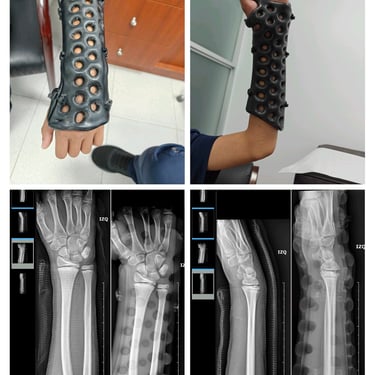

Yesos Ortopédicos Impresos en 3D en Panamá

Los yesos ortopédicos impresos en 3D son una alternativa moderna a los yesos de yeso o fibra de vidrio. Su diseño personalizado mejora confort, higiene, ajuste anatómico y seguimiento clínico, con evidencia científica creciente que respalda su seguridad y eficacia.

Alineación funcional: La adaptación anatómica favorece la inmovilización estable y puede mejorar parámetros radiográficos en fracturas de muñeca y antebrazo (Katt et al., 2021).

Radiografías sin retirar el yeso: El material es radiolúcido, por lo que es posible monitorizar la consolidación sin cortes ni sierras.

¿Se pueden tomar radiografías a través del yeso? Sí. La radiolucidez permite controles sin retirar el dispositivo.